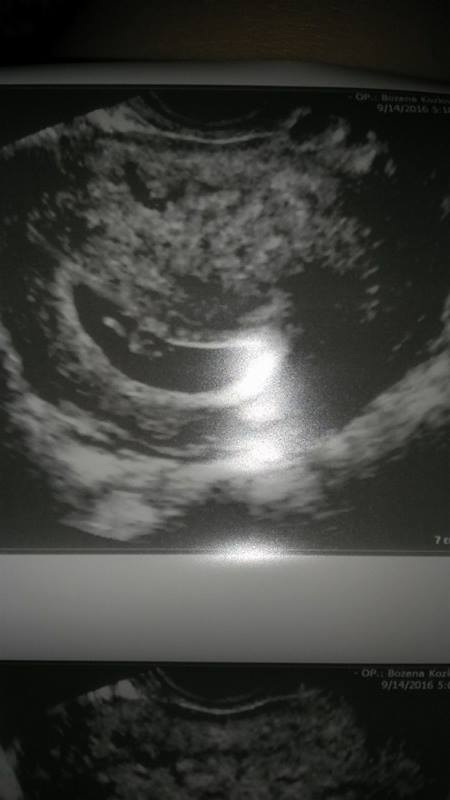

Hej ja już po wizycie wszystko w porządku, słyszałam serduszko pik pik:) wiek pokrywa się z wyliczeniami idealnie 6t 5d termin na 5 maj.

Z tego wszystko nie pamiętam wymiarów ale ciałko żółte bardzo ładne.

Zdjęcie może takie nie dokładne bo pierwszy raz dokładniej badała mierzyła ja tylko słuchałam czy w porządku i to serduszko bije jak szalone i nie drukneła mi zdjęcie potem wywiad i na koniec tak jeszcze raz mi zrobiła żebym mężowi mogła się pochwalić;)